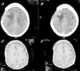

Postoperative abscess